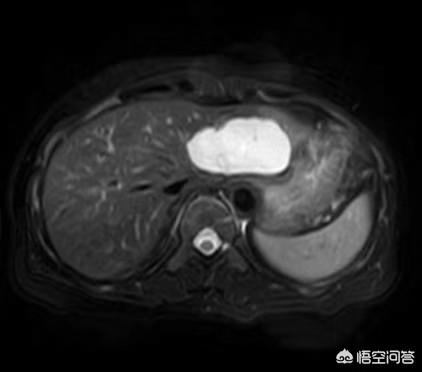

La plupart des hémangiomes caverneux sont découverts fortuitement par échographie lors d'un examen physique. Les lésions typiques présentent des images plus caractéristiques à l'échographie, au scanner et à l'IRM, et le diagnostic qualitatif n'est pas difficile. L'échographie et la tomodensitométrie permettent d'obtenir un rehaussement précoce et tardif, tandis que l'imagerie par résonance magnétique (IRM) T2 montre un "signe d'ampoule" (ci-dessous).